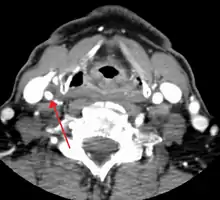

Section of carotid artery with plaque. Blood flows from the common carotid artery(bottom), and divides into the internal carotid artery (left) and external carotid artery (right). The atherosclerotic plaque is the dark mass on the left

Section of carotid artery with plaque. Blood flows from the common carotid artery(bottom), and divides into the internal carotid artery (left) and external carotid artery (right). The atherosclerotic plaque is the dark mass on the left

One of several different imaging modalities, such as a computed tomography angiogram (CTA)[18][19][20] or magnetic resonance angiogram (MRA) may be useful. Each imaging modality has its advantages and disadvantages - Magnetic resonance angiography and CT angiography with contrast is contraindicated in patients with chronic kidney disease, catheter angiography has a 0.5% to 1.0% risk of stroke, MI, arterial injury or retroperitoneal bleeding. The investigation chosen will depend on the clinical question and the imaging expertise, experience and equipment available.[21]